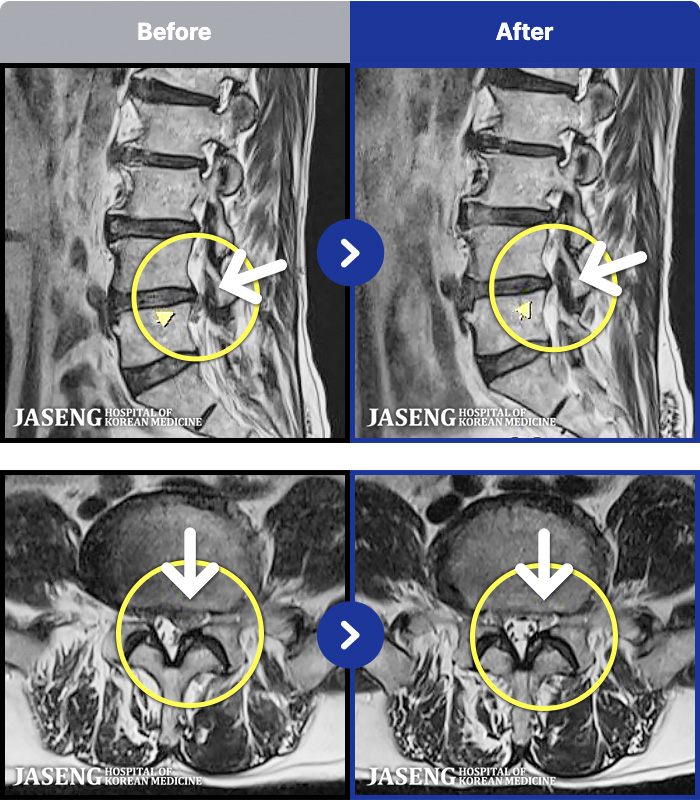

1,293 MRI ũ ʸ Ȯϼ.